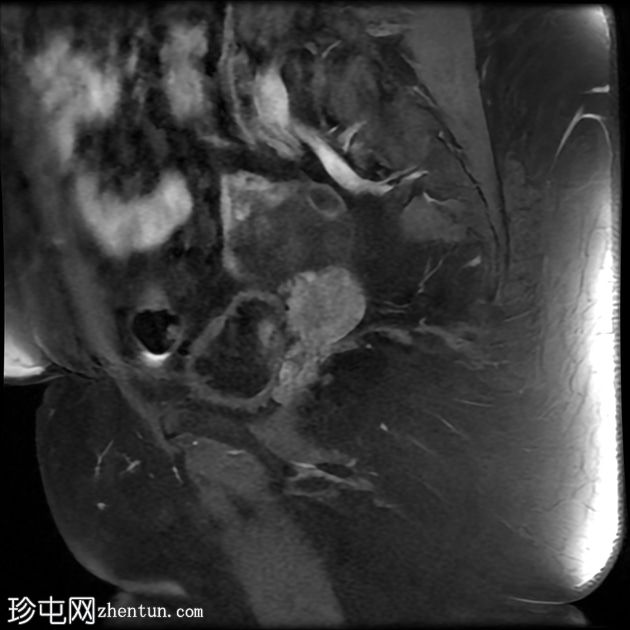

MRI

矢状位

T2加权像

左侧卵巢增大,呈弥漫性低T1信号和高T2信号,可见周边卵泡,部分卵泡除周边卵泡周围有环状强化外,无明显实质强化。左侧附件蒂呈漩涡状,提示卵巢扭转。